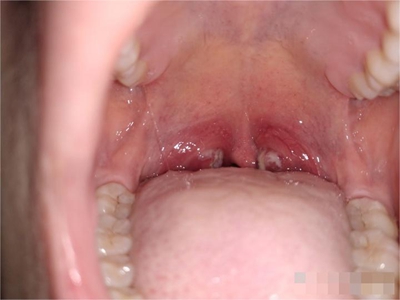

化脓性扁桃体炎扁桃体发红肿胀图

化脓性扁桃体炎患者口咽两侧的扁桃体充血发红,表面没有溃烂面,伴有咽痛,咽痛开始于一侧,继而双侧咽部均明显疼痛,吞咽时明显加剧。